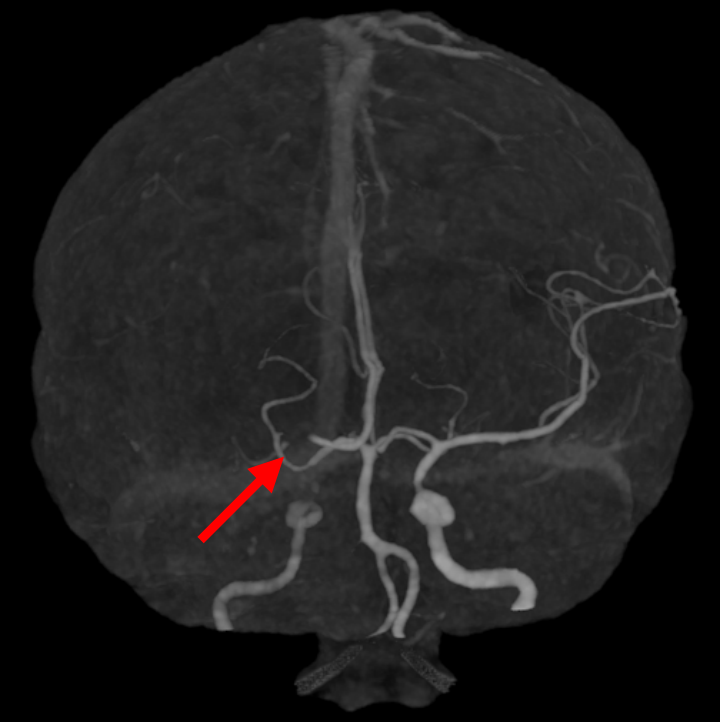

图1 图2

患者头颈部CTA(图1.右侧大脑中高密度影;图2.右侧颈内动脉末端、大脑中动脉闭塞)